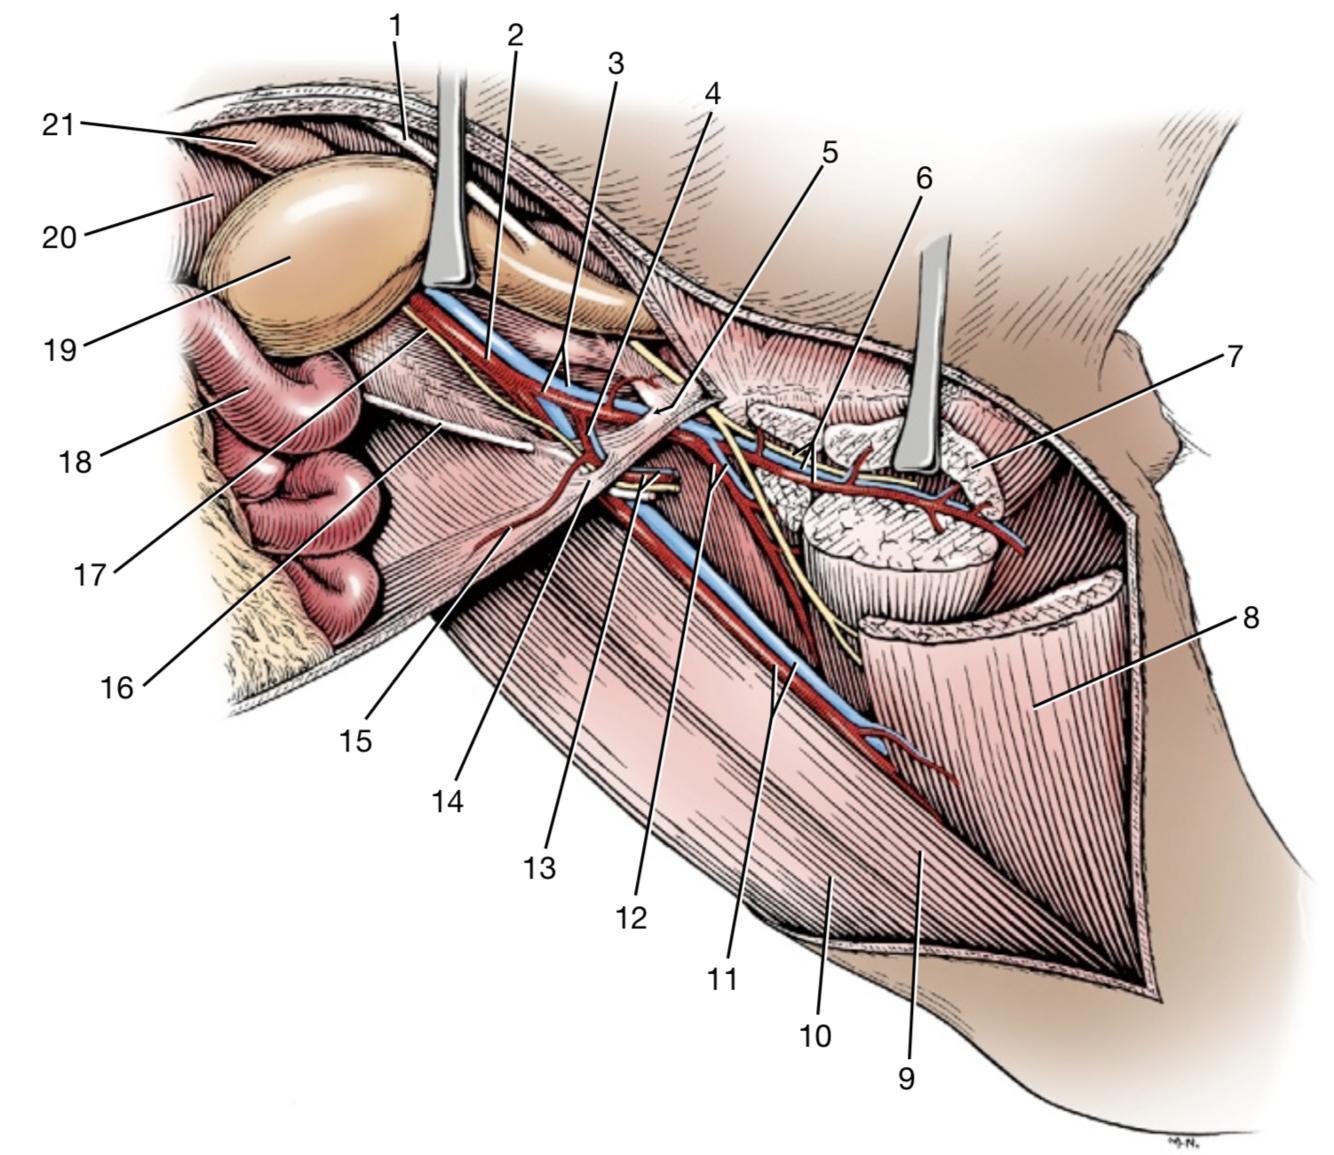

1

A

Crus mediale

6

Q

2

A

Crus laterale

7

Q

3

A

A./v. pudenda externa

8

Q

4

A

A./v. femoralis

9

Q

5

A

Processus vaginalis

10

Q

6

A

A./v. pudenda externa

11

Q

1

A

Crus mediale

12

Q

2

A

Crus laterale

13

Q

3

A

A./v. pudenda externa

14

Q

5

A

Processus vaginalis

15

Q

6

A

M. obliquus internus abdominis

16

Q

Lig. Inguinalis

A

17

Q

3

A

A./v. profunda femoris

- Ex a./v. iliaca externa

- Branches:

- Tr. pudendoepigastrica

- A. epigastrica caudalis

- A. circumflexa femoris medialis

18

Q

4

A

Tr. pudendoepigastrica

- Branches:

- A. pudenda externa

- A. epigastrica caudalis

19

Q

13

A

A./v. pudenda externa

- Through canalis inguinalis

- Branches: a. epigastrica caudalis superficialis

20

Q

15

A

A. epigastrica caudalis

- Supplies m. rectus abdominis

- Through canalis inguinalis

- Branches:

- **A. labialis/scrotalis ventralis